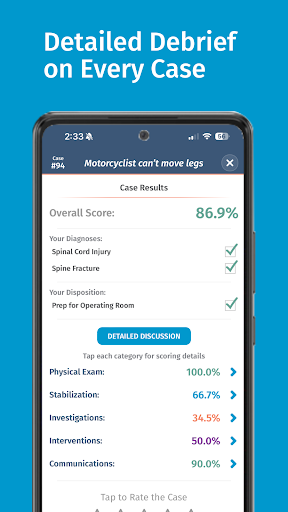

• Điểm số chi tiết và phân tích toàn bộ trường hợp - tìm hiểu điểm mạnh và điểm yếu của bạn

Các trường hợp có thể lặp lại vô hạn của Full Code đo lường các kỹ năng trong cả chẩn đoán và quản lý, cho phép bạn học hỏi từ những sai lầm của mình trong một môi trường không có rủi ro. Xây dựng năng lực để bạn có thể đối mặt với các trường hợp thực tế phức tạp một cách tự tin.